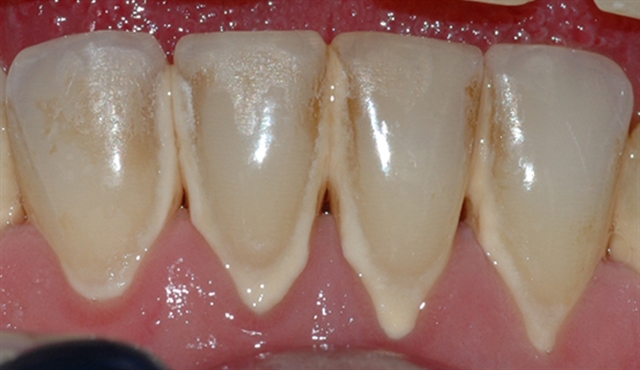

• perio stor 6

perio stor 6

Bildet viser et nærbilde av tennene i underkjeven med tannsten og misfarging.

• perio stor 7

perio stor 7

Bildet viser forholdene i underkjeven etter at tannsten og misfarging er fjernet